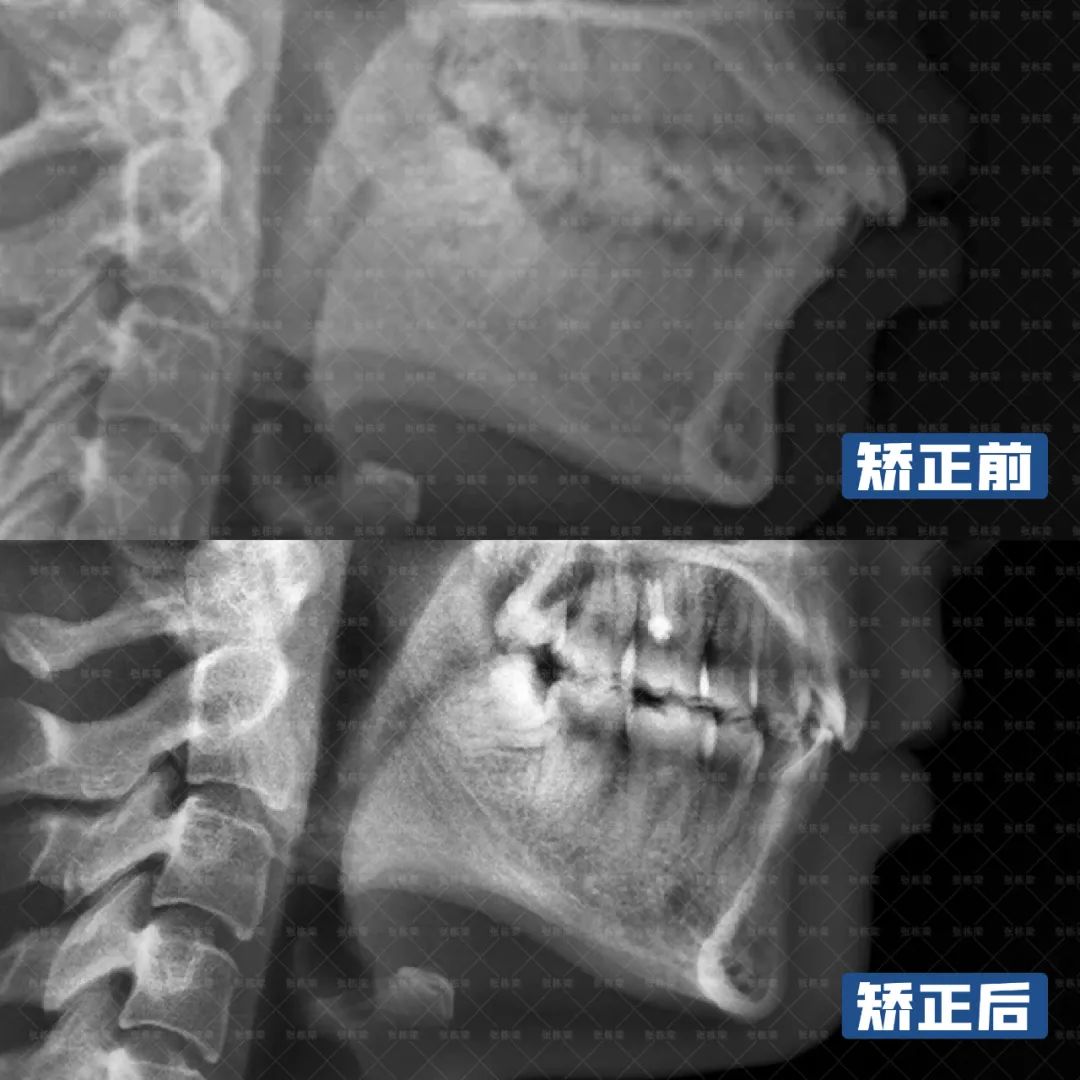

从牙片资料看,是典型的双颌牙性前凸问题,上下牙齿明显的向唇侧倾斜,导致面型的前凸。

整个矫正历时2年半的时间,上下前牙都收回去了,覆合覆盖正常、上下中线对齐、咬合都是I类关系。